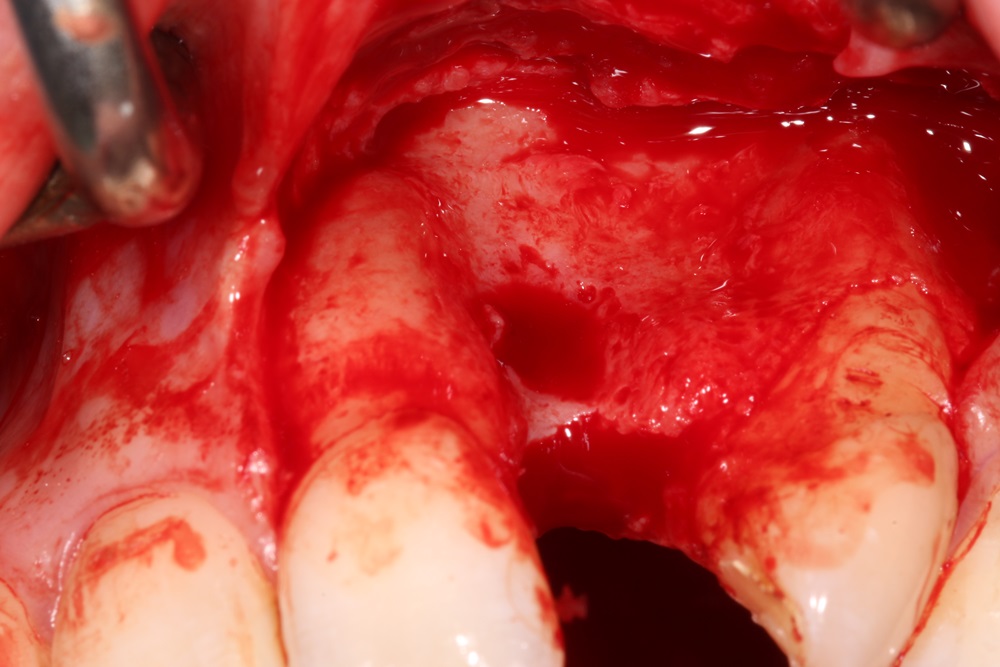

3/28 - Clinical situation after removal of Rochette showed clearly extensive hard and soft tissue volume lossBlock augmentation with maxgraft® in the maxilla - Dr. R. Cutts

5/28 - 6 months post extraction the block augmentation was performed. Large flap from the mesial of the upper left 1 to distal upper left 3 with a remote palatal and periosteal relieving incisionBlock augmentation with maxgraft® in the maxilla - Dr. R. Cutts